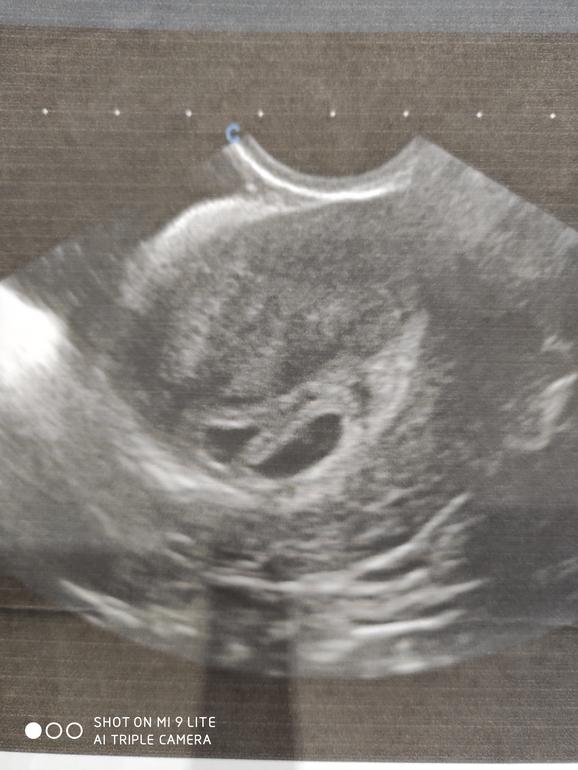

. И у нас появляется любимец 🥰😂 А в начале октября я узнаю, что беременна. И в этот же день младшей дочери поставили порок сердца, операция после новогодних праздников. С мужем поговорили и решили , что у нас будет 3 ребенок. Но... Через неделю делаю УЗИ, чтобы подтвердить маточную беременность и там два!!!! плодных яйца. Хорошо я лежала😜 Состояние шока несколько дней. Сколько раз представляла, а что если двойня!? И на тебе. На данный момент очень им💓💓 рада и переживаю т. к. есть иногда тонус.

Последнее УЗИ делали через живот, поэтому качество не очень.

Ну и размеры на срок 7 с половиной недель.